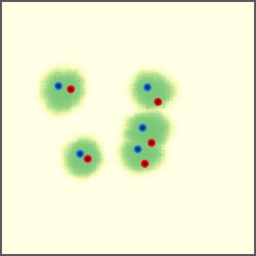

Shift-Invariant Tracking. The POINT network benefits from the shift invariant property of the convolution operation, which makes it less sensitive to the in-plane offset of the DRRs. Figure 8 shows some tracking results from the POINT network. Here the odd rows show the (a) X-ray and (b-d) DRR images. The heatmap below each DRR shows the tracking result between this DRR and the leftmost X-ray image. The red and the blue marks on the X-ray and DRR images denote the POIs. The red and the blue marks on the heatmaps are the ground truth POIs and the tracked POIs, respectively. The green blobs are the heatmap responses and they are used to generate the tracked POIs (blue) according to Equation (7). The numbers under each DRR denote the mPD scores before and after the tracking. As we can observe that the tracking results are consistently good, no matter how much initial offset there is between the DRR and the X-ray image. This shows that our POINT network indeed benefits from the POI convolution layer and provide more consistent outputs regardless of the in-plane offsets.

Refer to caption

(a)

(b) 13.6 \rightarrow 7.3

(c) 22.9 \rightarrow 9.0

(d) 37.1 \rightarrow 7.8

(e)

(f) 19.5 \rightarrow 8.7

(g) 26.0 \rightarrow 9.5

(h) 41.1 \rightarrow 11.4

(b)

(c)

(d)

Figure 8: POI tracking results. (a) X-ray image. (b-d) DRR images with different in-plane offsets. The heatmaps of the tracking results are all aligned with the X-ray images and appear similar, showing the shift-invariant property.